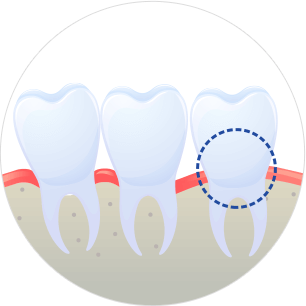

사랑니가 올바르게 난 경우

밖으로 올바르게 난 사랑니는 위생관리가 잘 되면 별다른 문제를 일으키지 않아 진단에 따라 발치를 권유합니다.